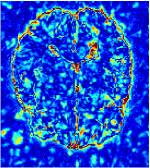

All the experiments are implemented on a Windows workstation with Intel Core i9 CPU at 3.3GHz and an Nvidia GTX-1080Ti GPU with 11GB of graphics card memory via TensorFlow Abadi et al. (2016). The parameters in the proposed network are initialized by using Xavier initialization Glorot and Bengio (2010). We trained the meta-learning network with four tasks synergistically associated with four different CS ratios: 10%, 20%, 30%, and 40%, and test the well-trained model on the testing dataset with the same masks of these four ratios. We have 300 training data for each CS ratio, which amount to total of 1200 images in the training dataset. The results for and MR reconstructions are shown in Tables 5.4 and 5.4 respectively. The associated reconstructed images are displayed in Figures 1 and 3. We also test the well-trained meta-learning model on unseen tasks with radio masks for skewed ratios: 15%, 25%, 35%, and random Cartesian masks with ratios 10%, 20%, 30% and 40%. The task-specific parameter for the unseen tasks are retrained for different masks with different sampling ratios individually with fixed task-invariant parameters . In this experiments, we only need to learn for three skewed CS ratios with radio mask and four regular CS ratios with Cartesian masks. The experimental training proceed on less data and iterations, where we performed on 100 MR images with 50 epochs. For example, for reconstructing MR images with CS ratio 15% radio mask, we fix the parameter and retrain the task-specific parameter on 100 raw data with 50 epochs, then test with renewed on our testing data set with raw measurement that sampled from radio mask with CS ratio 15%. The results associated with radio masks are shown in Table 5.4 and 5.4, Figure 2 and 4 for and images respectively. The results associated with Cartesian masks are list in Table 5.4 and reconstructed images are displayed in Figure 5.

In general supervised learning, training data need to be in the same or similar distribution, heterogeneous data exhibits different structure variations of features which hinders CNNs to extract features efficiently. In our experiments, raw measurements sampled from different ratios of compressed sensing display different levels of incompleteness, these undersampled measurements do not fall in the same distribution but they are related. Different sampling masks are shown at the bottom of Figure 1 and 2 may have complemented sampled points, in the sense that some of the points which sampling ratio mask does not sample have been captured by other masks. In our experiment, different sampling masks provide their own information from their sampled points so that four reconstruction tasks help each other to achieve an efficient performance. Therefore, it explains the reason that Meta-learning is still superior to conventional learning when the sampling ratio is large.

Qualitative comparison between conventional and Meta-learning methods are shown in Figure 1 and 3, which display the reconstructed MR images of the same slice for T1 and T2 respectively, we label the zoomed-in details of HGG in the red boxes. We observe the evidence that conventional learning is more blurry and lost sharp edges, especially in lower CS ratios. From the point-wise error map, we find meta-learning has the ability to reduce noises especially in some detailed and complicated regions comparing to conventional learning.

In this section, we test the generalizability of the proposed model that tests on unseen tasks. We fix the well-trained task-invariant parameter and only train for sampling ratios 15%, 25% and 35% with radio masks and sampling ratios 10%, 20%, 30% and 40% with Cartesian masks. In this experiment, we only used 100 training data for each CS ratio and apply a total of 50 epochs. The averaged evaluation values and standard deviations are listed in Table 5.4 and 5.4 for reconstructed T1 and T2 brain images respectively that proceed with radio masks, and Table 5.4 shows the qualitative performance for reconstructed T2 brain image that applied random Cartesian sampling masks. In T1 image reconstruction results, meta-learning improved 1.6921 dB in PSNR for 15% CS ratio, 1.6608 dB for 25% CS ratio, and 0.5764 dB for 35% comparing to the conventional method, which in the tendency that the level of reconstruction quality for lower CS ratios improved more than higher CS ratios. A similar trend happens in T2 reconstruction results with different sampling masks. The qualitative comparisons are illustrated in Figure 2, 4 and 5 for T1 and T2 images tested in skewed CS ratios in radio masks, and T2 images tested in Cartesian masks with regular CS ratios respectively. In the experiments that conducted with radio masks, meta-learning is superior to conventional learning especially at CS ratio 15%, one can observe that the detailed region in red boxes keeps edges and is more close to the true image, while conventional method reconstructions are hazier and lost details in some complicated tissue. The point-wise error map also indicates that Meta-learning has the ability to suppress noises.